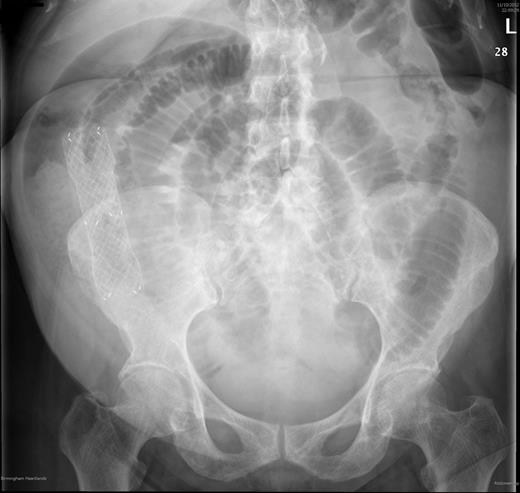

Abdominal X ray showed multiple distended loops of small bowel with a migrated stent inside small bowel Fig. 1.

Abdominal X ray taken shortly after presentation. Abdominal films show multiple dilated loops of small bowel with a visible stent in the abdomen.